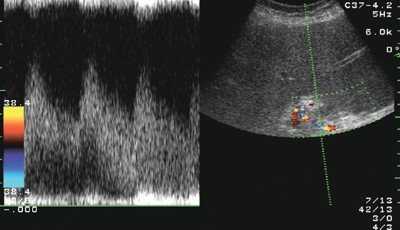

У больных циррозом печени, воздерживавшихся от употребления алкоголя, отмечалась тенденция к нормализации уровня печеночных ферментов: активность алкогольного гепатита была невысокой. Увеличение размеров правой доли печени было выражено в меньшей степени. ИР печеночной артерии превышал 0,7, что характерно для цирроза печени любой другой этиологии (рис. 1). Размеры селезенки, диаметр воротной вены и скорость воротного кровотока были такими же в контрольной группе. У больных в группе 3 различия с контрольной группой отсутствовали: сохранялись лабораторные признаки активного алкогольного гепатита (высокий уровень ГГТ, преобладание ACT над АЛТ), гепатомегалия и не характерно низкий для цирроза печени ИР печеночной артерии (0,59±0,05) (рис. 2).

Рис. 2. Эхограмма: спектр кровотока в печеночной артерии у больного циррозом печени с активным алкогольным гепатитом (ИР=0,47).